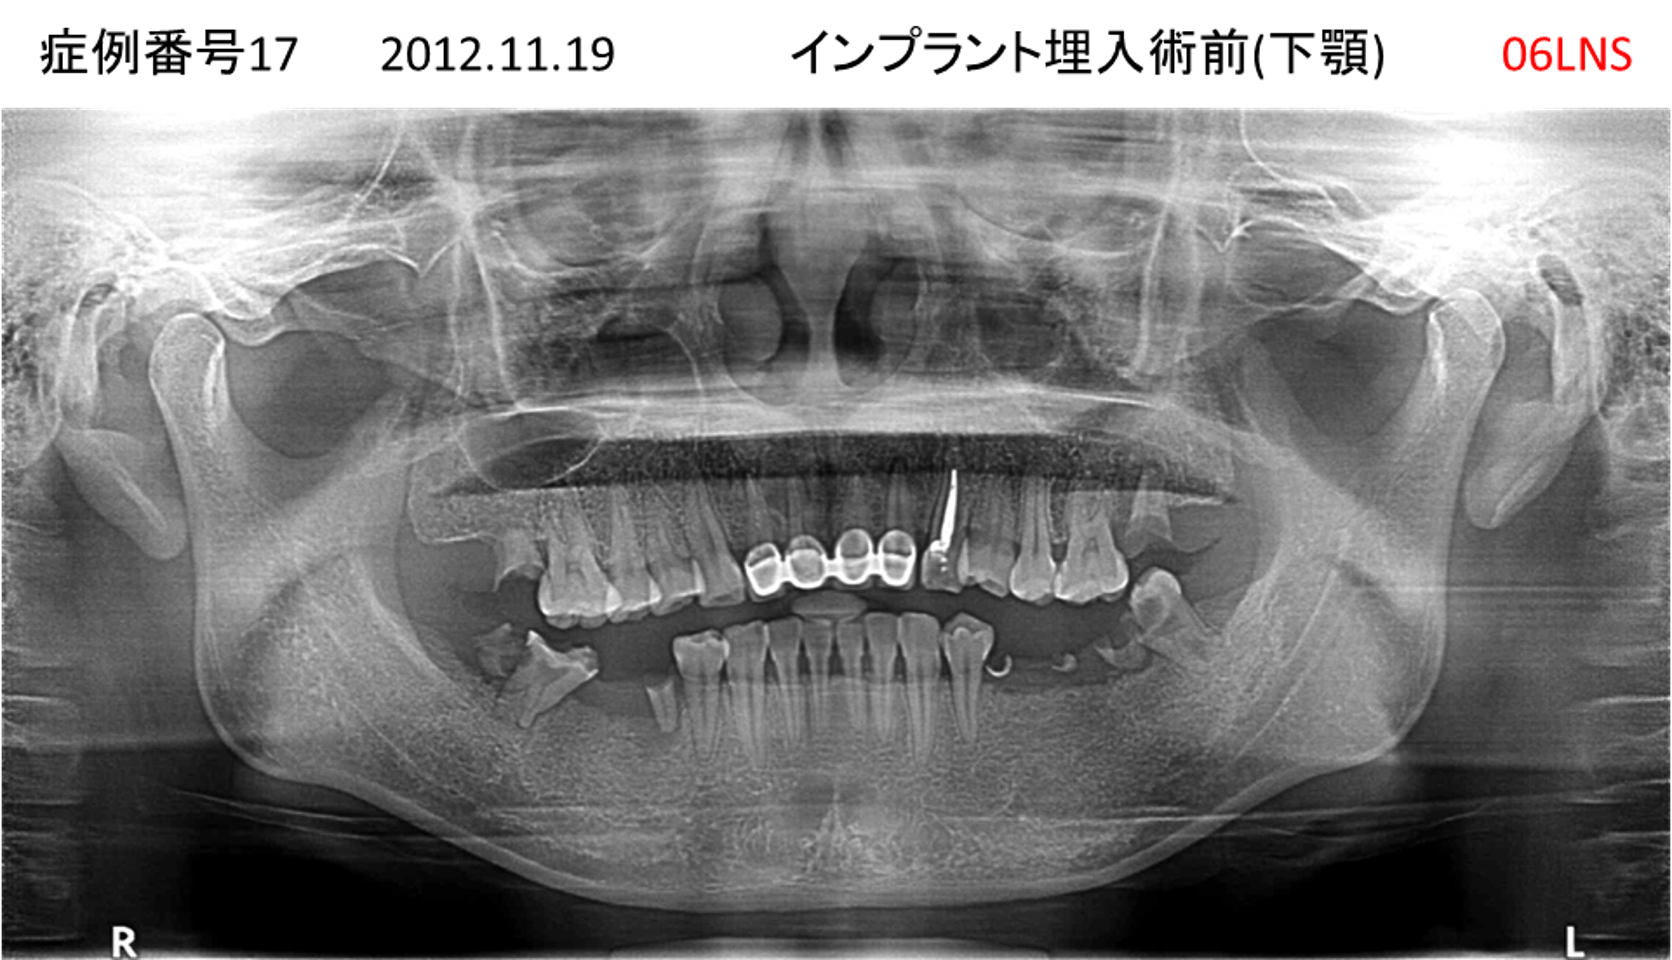

義歯が合わない、噛めない患者様のインプラント症例

| 治療名称 |

インプラントコーヌステレスコープ |

| 治療費用 |

270万円+税 |

| 治療期間 |

4か月 |

| 患者さんの症状(主訴) |

義歯が合わない、噛めない |

| 治療内容 |

インプラント、義歯作製(コーヌステレスコープ) |

| 治療結果 |

しっかり噛めるようになった。見栄えが良くなった。 |

| 治療の注意点(リスク/副作用) |

義歯が壊れた場合、インプラントが壊れた場合は再治療が必要 |